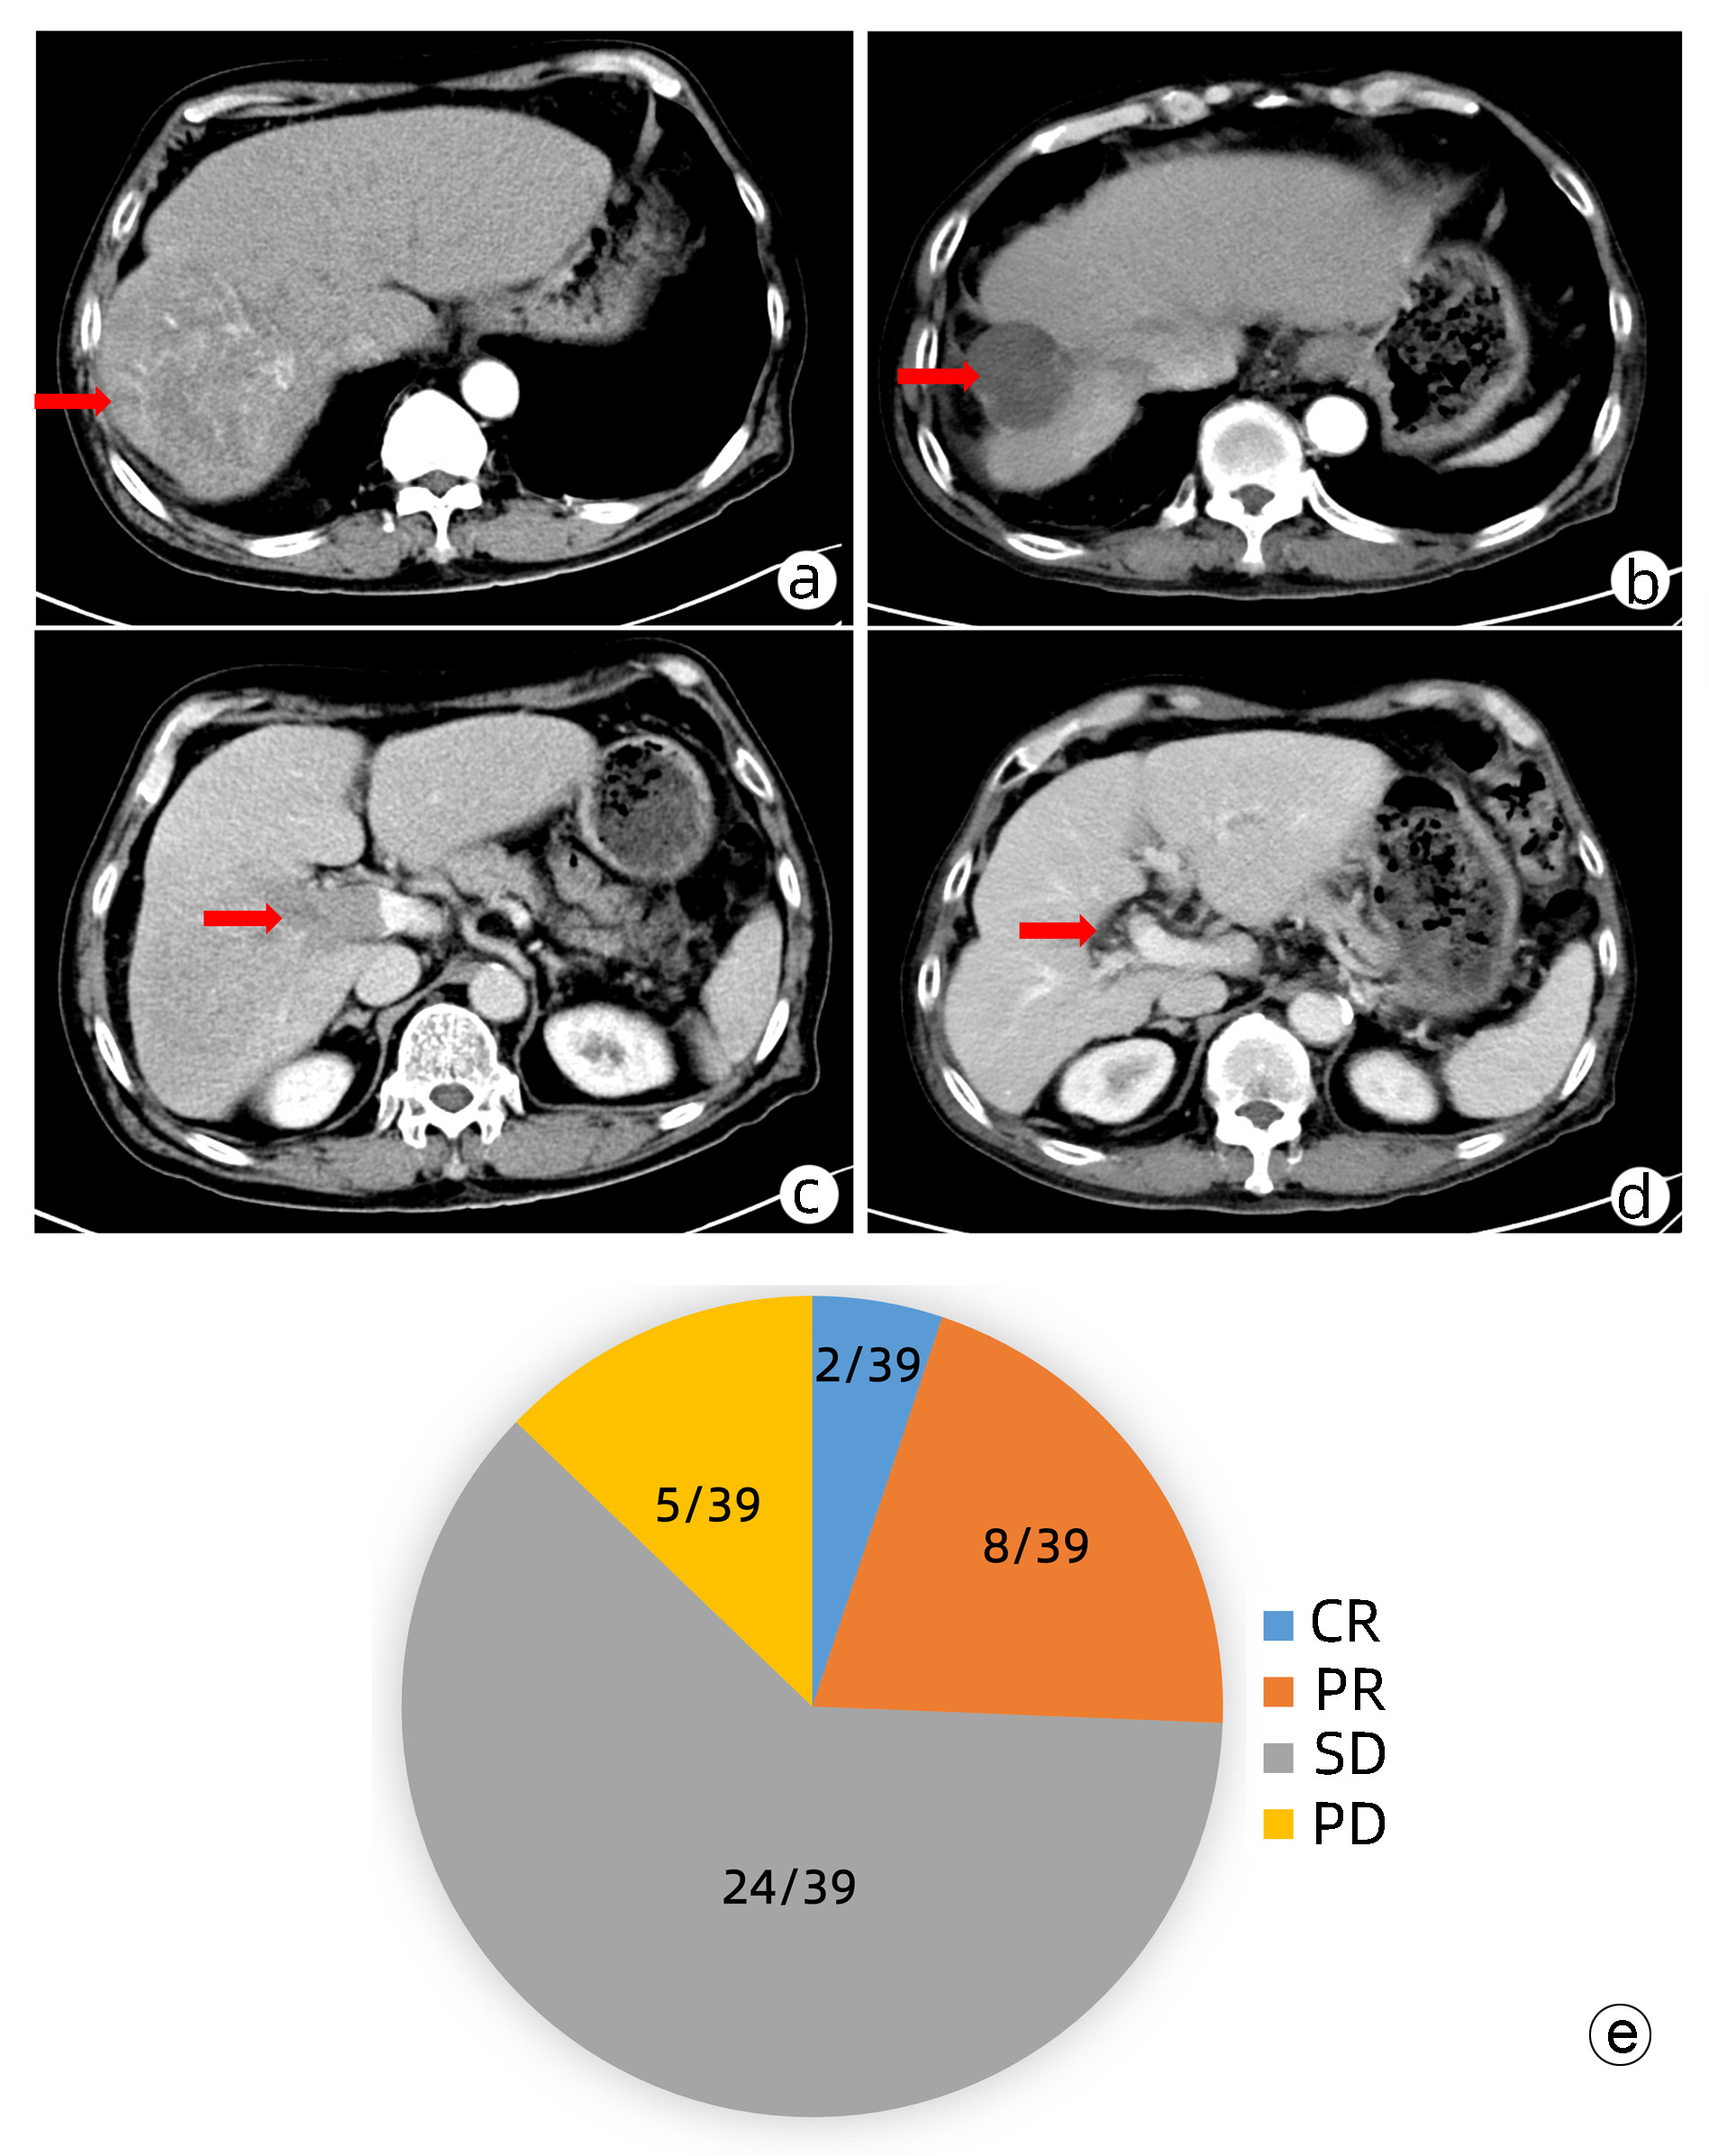

肝动脉灌注化疗及其综合治疗方案对中晚期肝细胞癌患者的临床疗效及预后因素分析

戴文聪, 臧梦雅, 袁国盛, 李祺, 李榕, 李文利, 董书语, 陈锦章

2023, 39(7): 1592-1599. DOI: 10.3969/j.issn.1001-5256.2023.07.013

摘要:

目的  本研究旨在观察FOLFOX方案持续肝动脉灌注化疗(HAIC)及其综合治疗方案对中晚期肝细胞癌患者的临床疗效并分析影响预后的因素。  方法  回顾性收集南方医科大学南方医院2018年9月—2021年11月行FOLFOX方案持续HAIC的66例中晚期肝细胞癌患者临床资料。观察治疗后患者的客观缓解率、疾病控制率、中位无疾病进展生存时间(mPFS)和中位生存时间(mOS)并记录治疗相关不良反应。针对伴有门静脉癌栓的患者,评价治疗对门静脉癌栓的疗效。采用Kaplan-Meier法进行生存分析。采用Cox回归分析影响预后的因素。  结果  按照RECIST1.1标准,FOLFOX-HAIC及其综合治疗方案治疗66例中晚期肝细胞癌患者的客观缓解率和疾病控制率分别为33.3%(22/66)、86.4%(57/66),mPFS和mOS分别为8.2个月和22.1个月。其中39例合并门静脉癌栓的肝癌患者中完全缓解2例,部分缓解8例,稳定24例,进展5例。客观缓解率为25.6%(10/39),疾病控制率为87.2%(34/39)。不良反应主要为消化道反应16.7%(11/66)、发热12.1%(8/66)、肝区疼痛10.6%(7/66)、骨髓抑制3.0%(2/66)和造影剂过敏3.0%(2/66)。无Ⅳ级以上的毒副反应。无并发症导致的死亡。Cox分析显示肝外转移(HR=2.668, 95% CI:1.357~5.245)和凝血酶原时间(HR=1.282, 95%CI:1.080~1.630)是影响患者PFS的独立危险因素(P值均<0.05), AST水平(HR=1.008, 95%CI:1.002~1.013)和凝血酶原时间(HR=1.303, 95%CI:1.046~1.630)是影响患者OS的独立危险因素(P值均<0.05)。  结论  FOLFOX-HAIC及其综合治疗方案治疗中晚期肝细胞癌有一定的疗效,不良反应可控。